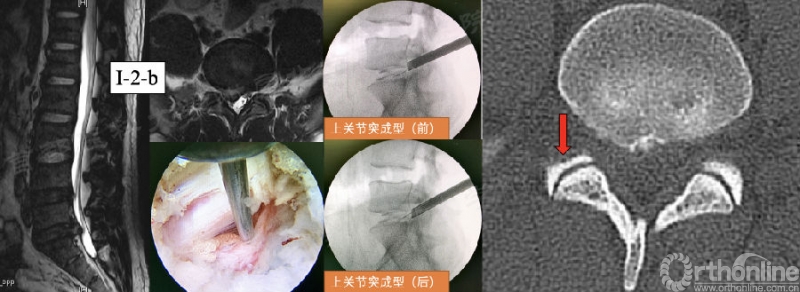

第25例:男,32岁,L5/S1 LDH(I-2-b)。

第54例:男,47岁,L5/S1 LDH(I-2-b)伴钙化。

第68例:女,44岁。L5/S1 LDH(I-2-c)。